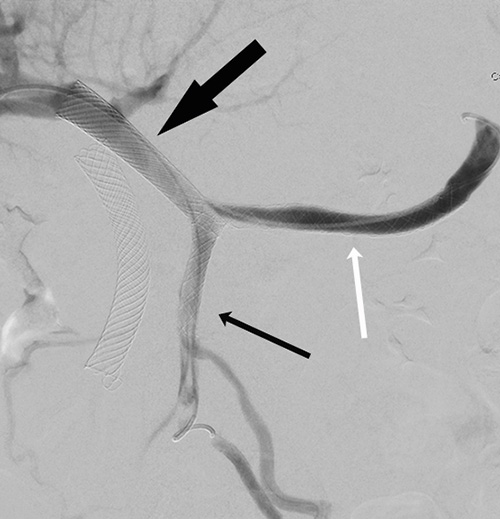

En annan relativt ny metod är selektiv intern radioterapi (SIRT), som innebär att radioaktiva mikrosfärer deponeras lokalt via en arteriellt inlagd kateter för behandling av levertumörer [7] (Figur 3). För att tillförsäkra maximal effekt och samtidigt säkerhet vid injektion av dessa radioaktiva mikrosfärer utförs angiografisk kartläggning av kärl och eventuell embolisering av extrahepatiska artärgrenar ca 1 vecka innan behandling ska ske. Noggrann planering för tillverkning och transport av dessa radioaktiva mikrosfärer är essentiell liksom strålskyddsåtgärder vid hantering och behandling.

Figur 3. Karcinoidmetastas i levern. Delvis nekrotisk metastas före SIRT (selektiv intern radioterapi) (övre bilden). Oförändrad storlek av nekrotisk metastas 2 år efter SIRT-behandling (undre bilden).